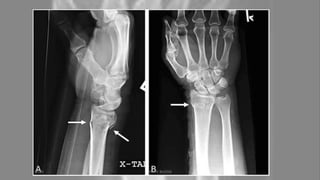

Diagnosis is most often made

upon interpretation of

posteroanterior and lateral views

alone.

(X-ray of a Colles' fracture of the

left wrist accompanied by an ulnar

styloid fracture.)

The classic Colles fracture has the following characteristics;

• Transverse fracture of the radius.

• 2.5 cm (0.98 inches) proximal to the radiocarpal joint.

• dorsal displacement and dorsal angulation, together with the radial tilt.

Other characteristics on plain radiographs may include:

• Radial shortening.

• Loss of ulnar inclination.

• Radial angulation of the wrist.

• Comminution at the fracture site.

• Associated fracture of the ulnar styloid process in more than 60% of cases.